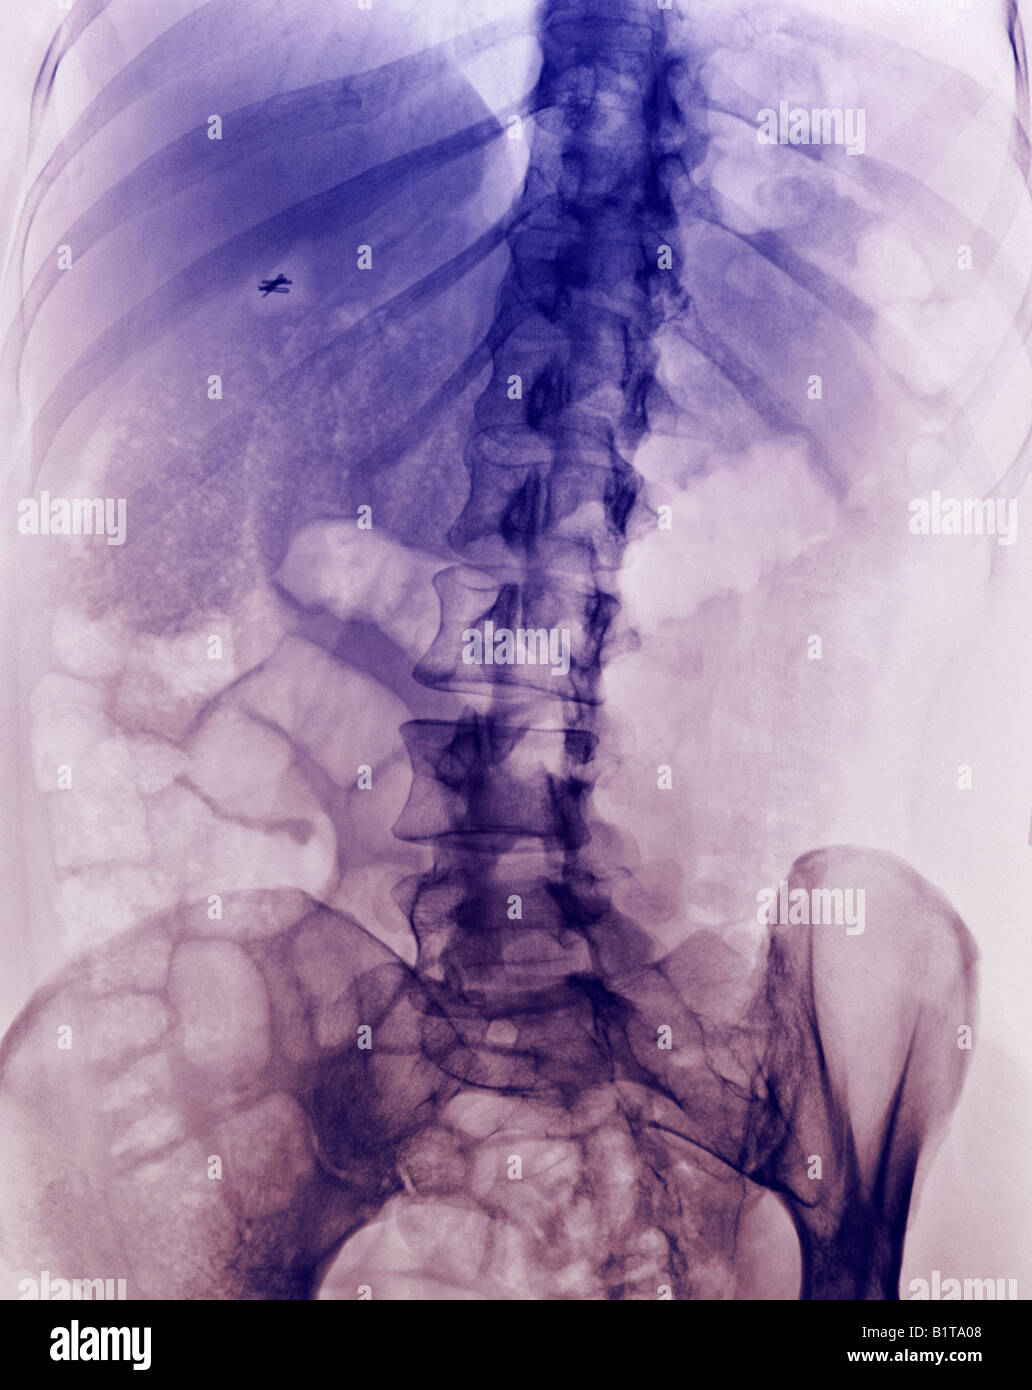

From www.alamy.com

X ray normal lumbar spine hires stock photography and images Alamy What Are Surgical Clips In An Xray Some surgical clips are meant to remain after surgery. With these, the incidence of retained small and complex surgical instruments such as broken. Surgical clips used in laparoscopic tubal ligation procedures. If you google your very own topic title word for word. The following are more important to be recognized by. The reason i ask is there is meant to. What Are Surgical Clips In An Xray.